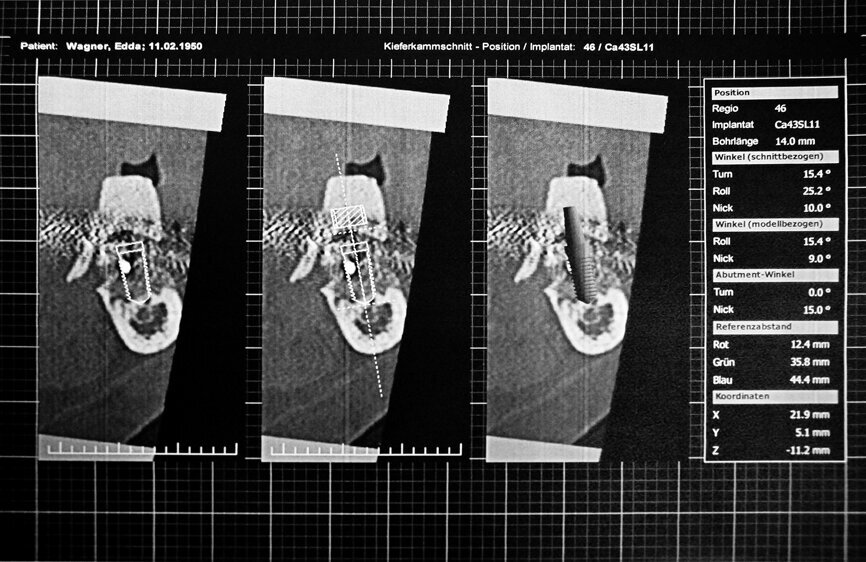

Fig. 3 : Coupe sagittale au niveau du site implantaire 46 planifié.

Les conditions anatomiques devaient permettre la pose d’au moins quatre implants dans une position idéale pour la restauration prothétique (Fig. 3). Une fois qu’implant avait été planifié, il était aisé de voir l’os cortical vestibulaire et lingual.

Apres l’analyse du volume osseux, les implants ont été planifiés sur la face linguale, et la plateforme de l’implant a été virtuellement positionnée à hauteur de la partie coronaire de la crête alvéolaire vestibulaire (Fig. 4). La caractéristique principale de la fabrication du guide chirurgical est le positionnement sur et la fixation stable des manchons de forage dans le guide. Pour obtenir le gabarit de forage, les manchons de forage ont été mis en place sur les modèles en plastique fabriqués au moyen d’un procédé additif (Fig. 5).